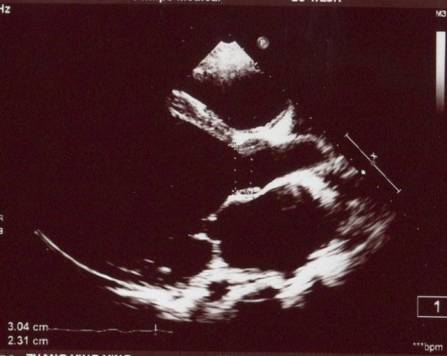

超声心动图

►超声心动:LA 36mm,LV 86mm,LVEF 20%,RV 24mm

►左房轻度增大,左室明显扩大成球形,左室壁弥漫性运动减弱,右房室不大,二尖瓣中大量返流